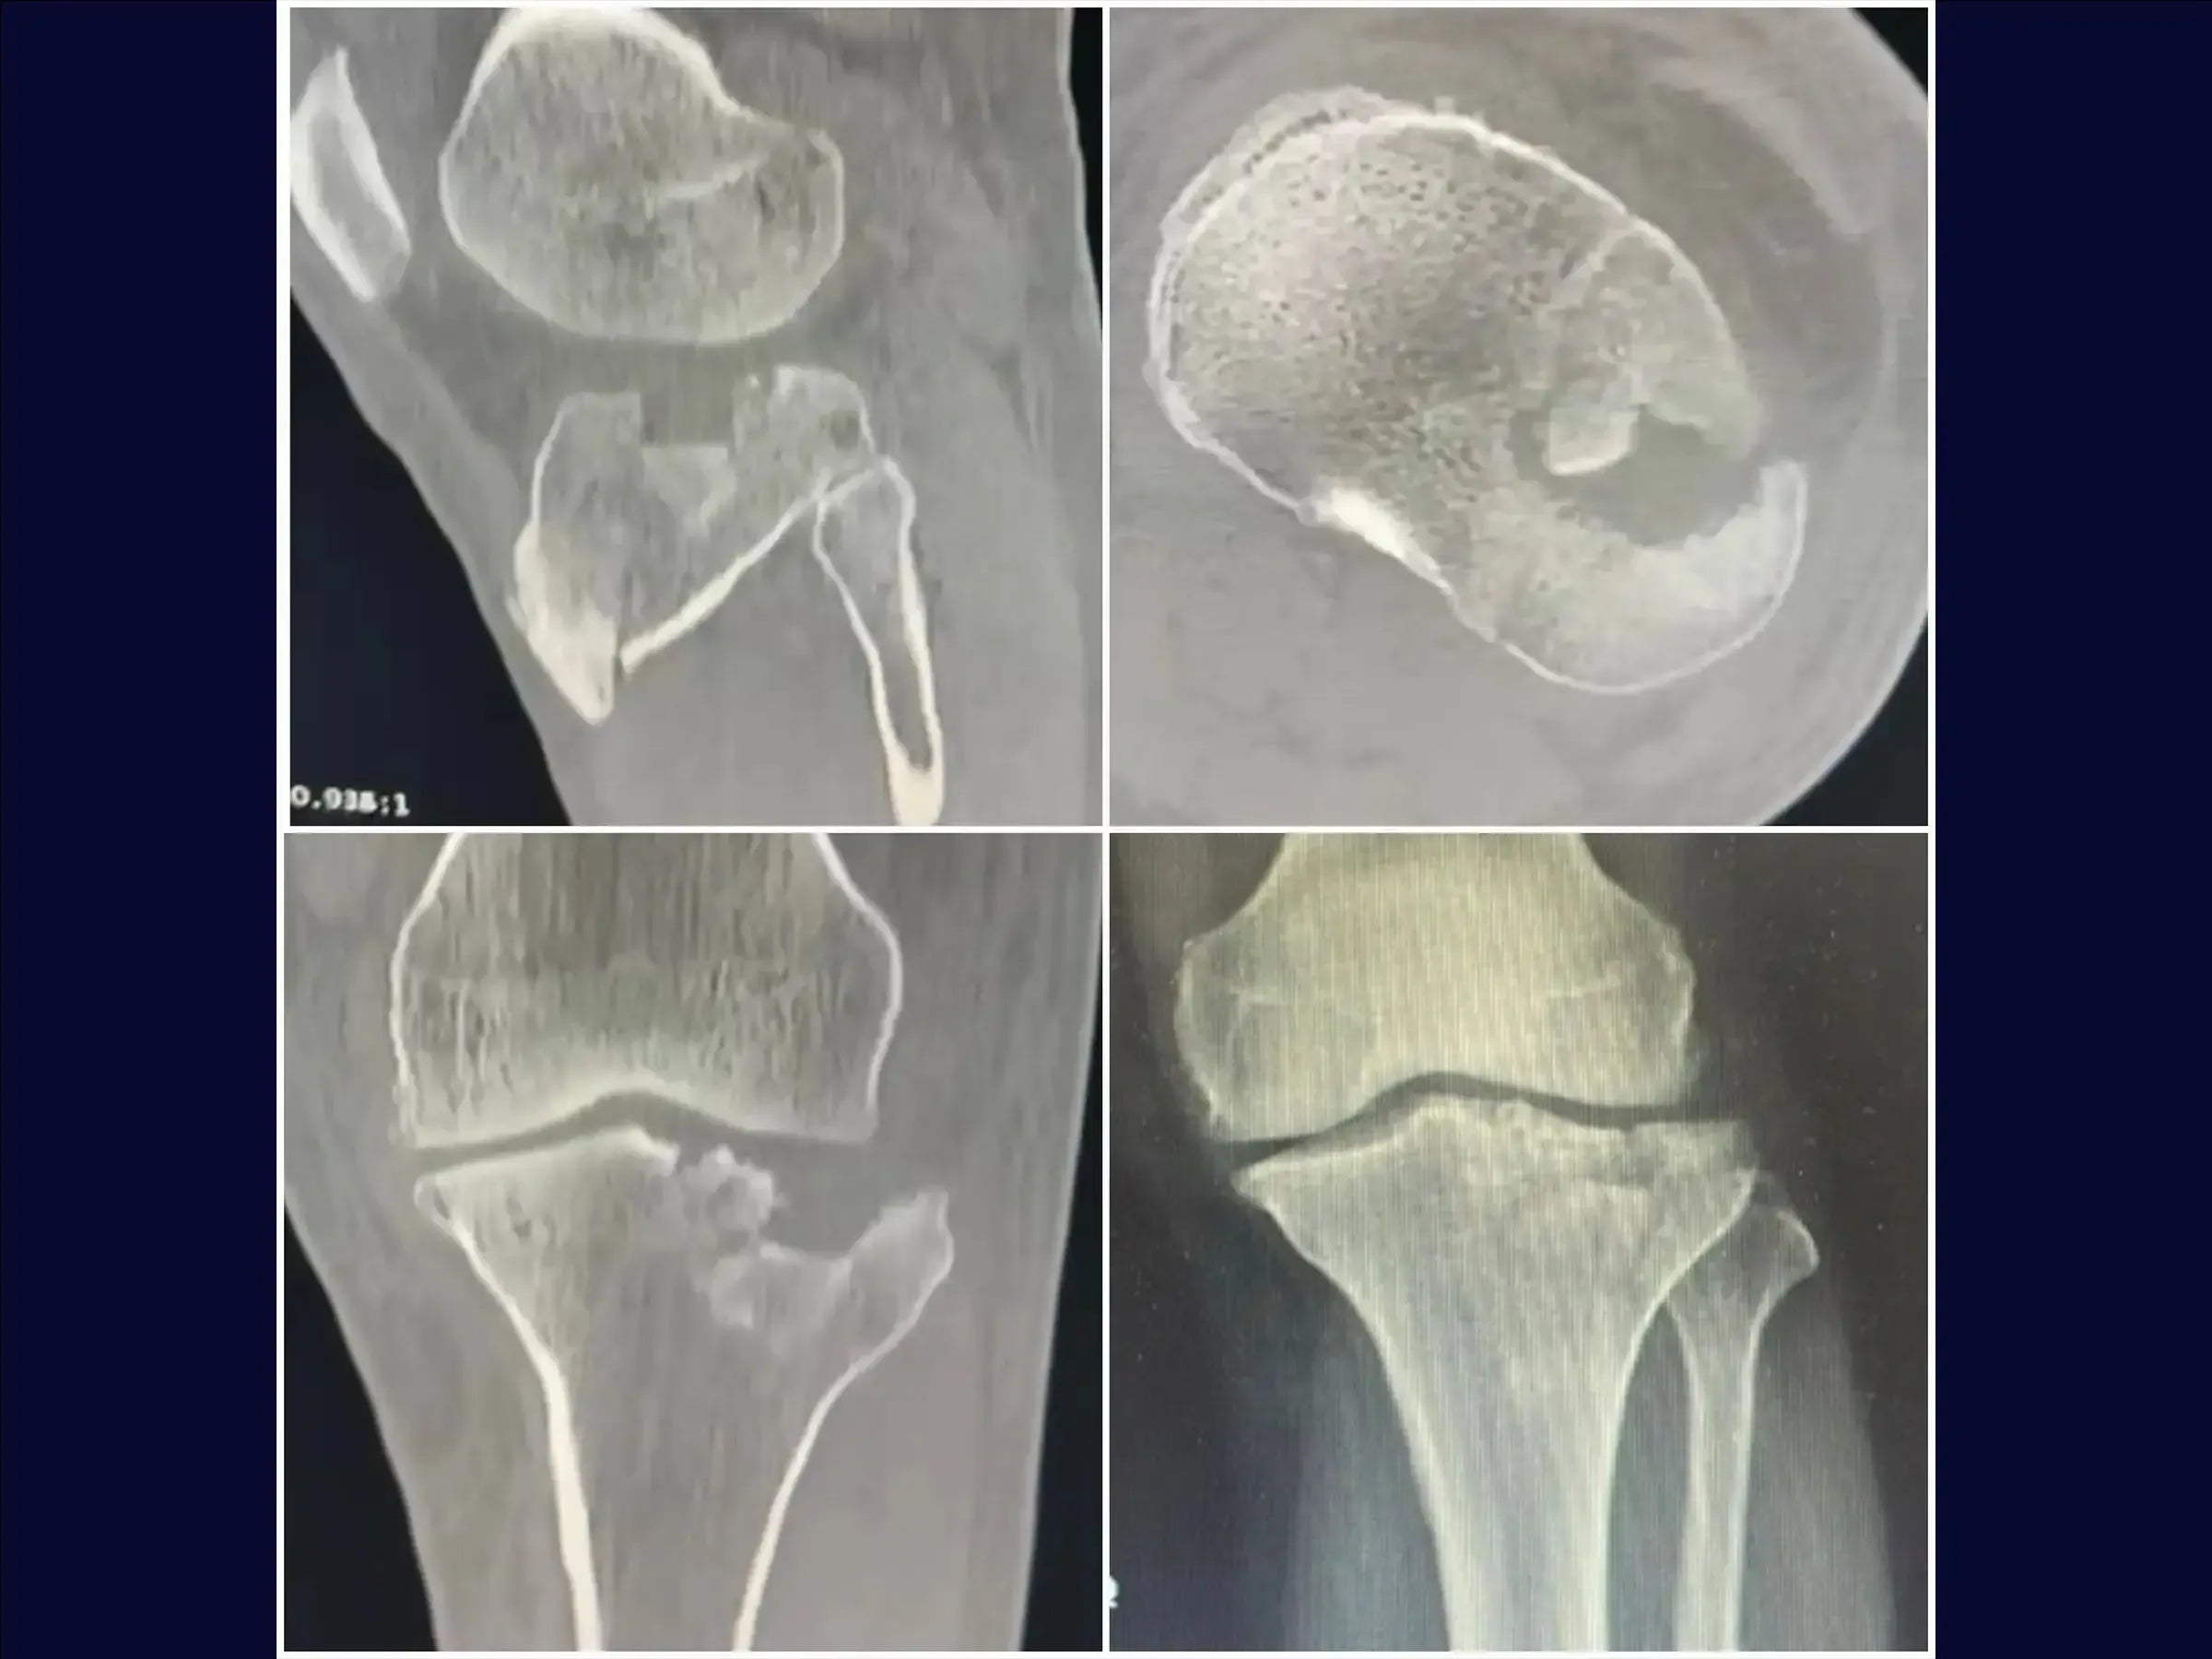

Domine o tratamento de fraturas do platô tibial com afundamento central. Este treinamento oferece uma imersão técnica na osteossíntese utilizando osteotomia incompleta e acesso anterolateral específico, apresentado em vídeo 4K sob a perspectiva cirúrgica, para restaurar a anatomia e a função articular.

- Osteossíntese de fraturas do platô tibial com afundamento central e cisalhamento incompleto.

- Manejo do Menisco e Exposição Articular: Preparo do menisco com fios de Vicryl e levantamento preciso para ampla exposição do afundamento, garantindo a integridade das estruturas.

- Osteotomia Elástica para Redução Anatômica: Abordagem de osteotomia incompleta que mantém a cortical anterolateral íntegra, permitindo o levantamento do fragmento afundado com retorno natural à posição.

- Estratégias de Enxertia Óssea: Protocolos para preenchimento da depressão com enxerto em grânulos, incluindo hipercorreção para acomodação e resistência, e uso de enxerto estrutural para suporte.

- PDF Detalhado: Resumo prático do procedimento, abordando: condição da fratura (platô tibial com afundamento central e cisalhamento incompleto); acesso cirúrgico anterolateral em "taco de hóquei"; preparação e dissecção detalhada; manuseio do menisco e osteotomia incompleta (elástica); levantamento da depressão e enxertia; fixação com parafusos canulados e placa; e fechamento por planos para restauração anatômica e tecidual, culminando em redução anatômica e boa estabilização.